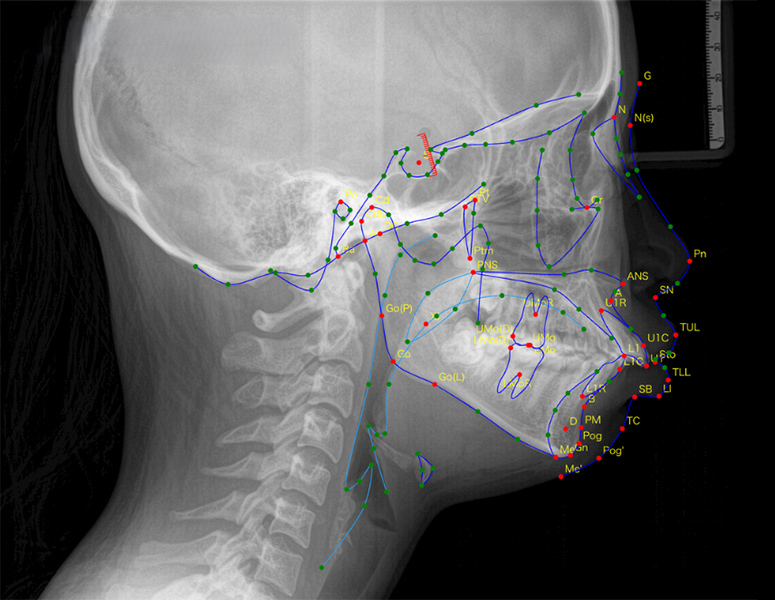

Industry-leading 159 landmarks measurement in seconds

Simply upload a cephalogram, and AI automatically traces facial appearance, skeleton, occlusion, soft tissue, and airway across 159 measurement points in seconds. Work that previously took over 30 minutes is dramatically streamlined.

Achieves standardization unaffected by experience or proficiency with specialist-level accuracy.

Manual corrections supported, achieving both efficiency and accuracy.